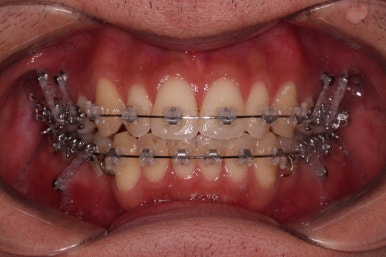

치료시작 6개월 정도 시점의 모습인데, 이정도만 해도 교정이 잘 된 듯 하지만 이제 시작입니다.

얼굴 모습 개선을 위해 해야 될 점들이 많습니다.

미니스크류도 일반적인 위치가 아니라 전반적인 치열의 높낮이를 조절하기에 용이한 위치에 갯수도 매우 많이 식립하게 됩니다.

한참을 셋팅한 방향으로 치열을 당겨줍니다.

중간평가를 자주 하게 됩니다.